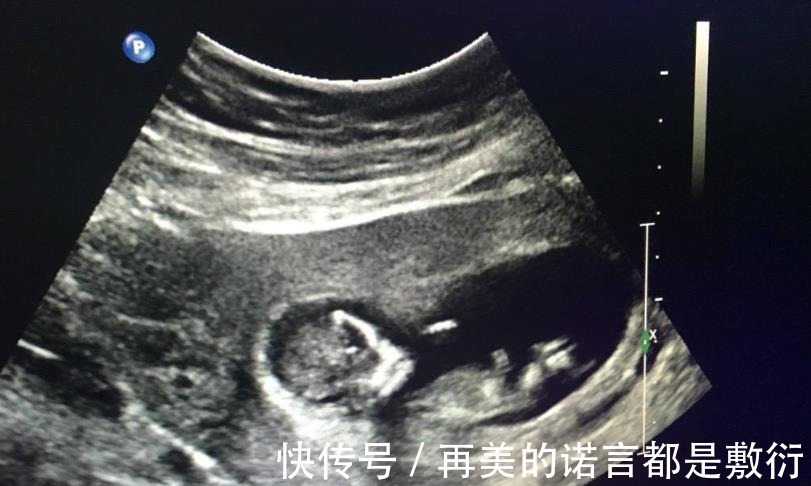

胎儿的性别是从受精卵开始就已经决定了,在孕初期无法看出胎儿的性别,而到了孕十二周,胎儿的性别特征才会一点点显现出来。怀孕十二周,腹中胎儿的不同性别有哪些区别?孕十二周,由于胎儿还处在生长发育阶段,其身长只有约9厘米,胎重23g左右,相当于3颗草莓的重量。这个阶段我们还只能看到胎心和胎芽,其他器官都还未发育成熟,而胎儿的性别器官已经开始发育,不过都还都未发育完全,因此就算此时通过B超检察胎儿性别,也不一定准确。并且医院有明确规定:不允许通过B超手段,检查胎儿性别,并且不允许医生提前告知胎儿性别,因此就算医生看得出来,也是会“守口如瓶”的。【 男孩|怀孕后,想知道胎儿性别是什么,可以尝试这些方法来鉴别】

5、孕16周性别显现比较明显孕十六周胎儿的性别器官才完全发育成熟,这时B超就可以相对准确地看出胎儿的性别了,但也是需要一些运气的,因为有时碰巧遇到胎儿背着身体或四肢遮挡住性别器官,那就没办法确认了。